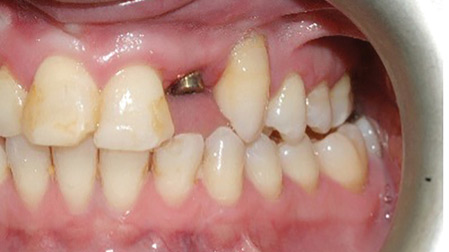

Transition From A Removable To A Fixed Implant-Supported Prosthesis: A Case Report

Abstract Incorporation of dental implants to support fixed and removable prostheses is an effective treatment modality for edentulous patients that provides enhanced patient function, comfort and overall quality of life in comparison to a conventional complete removable prosthesis. Both fixed and removable implant-supported prostheses for edentulous patients have specific indications although in many clinical situations … Read more